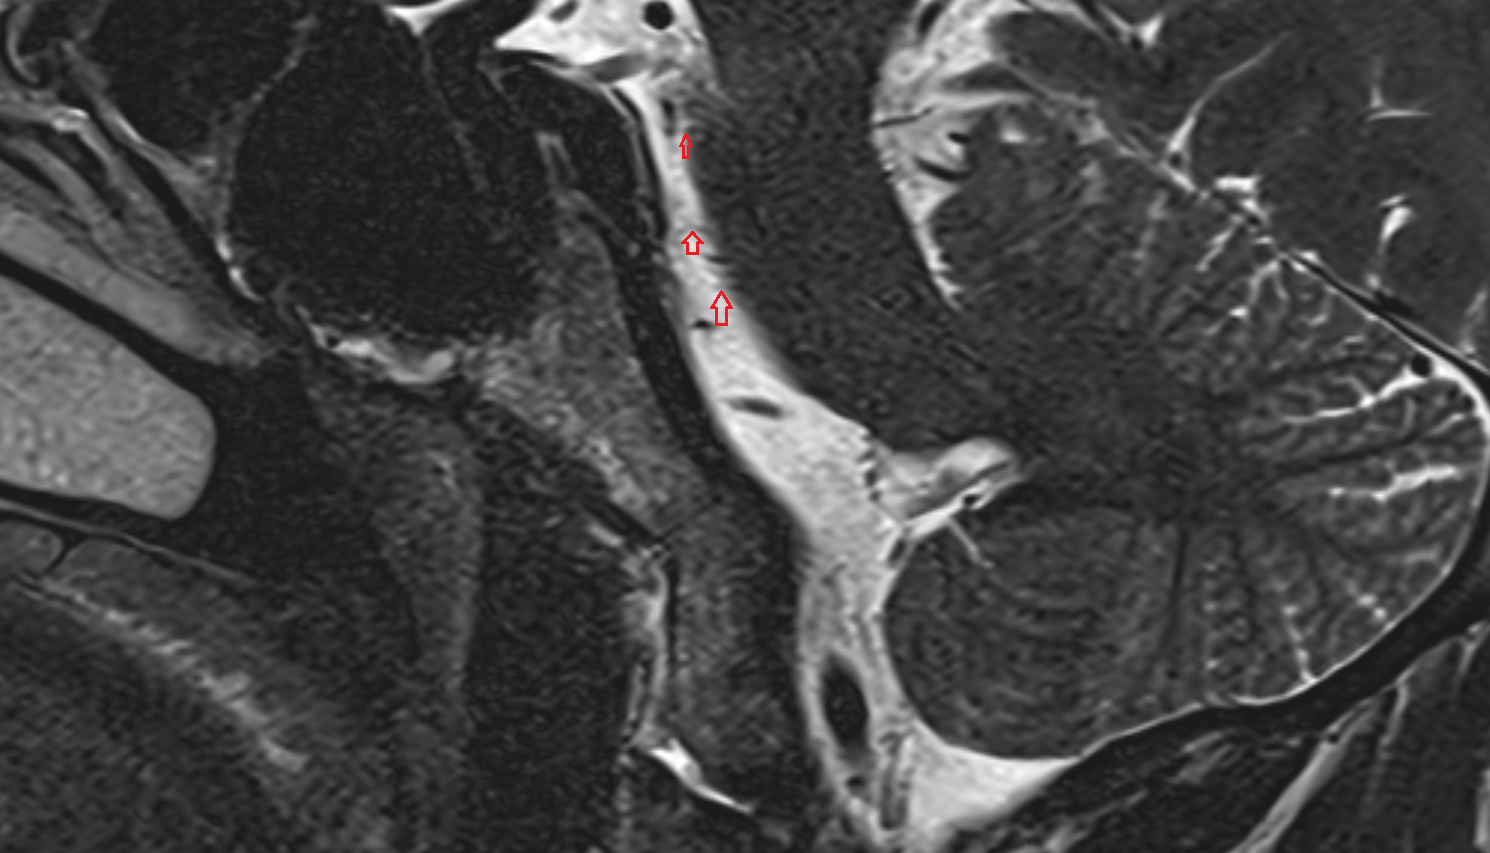

- Body of hippocampus

- Head of hippocampus

- Tail of hippocampus

- Hippocampus